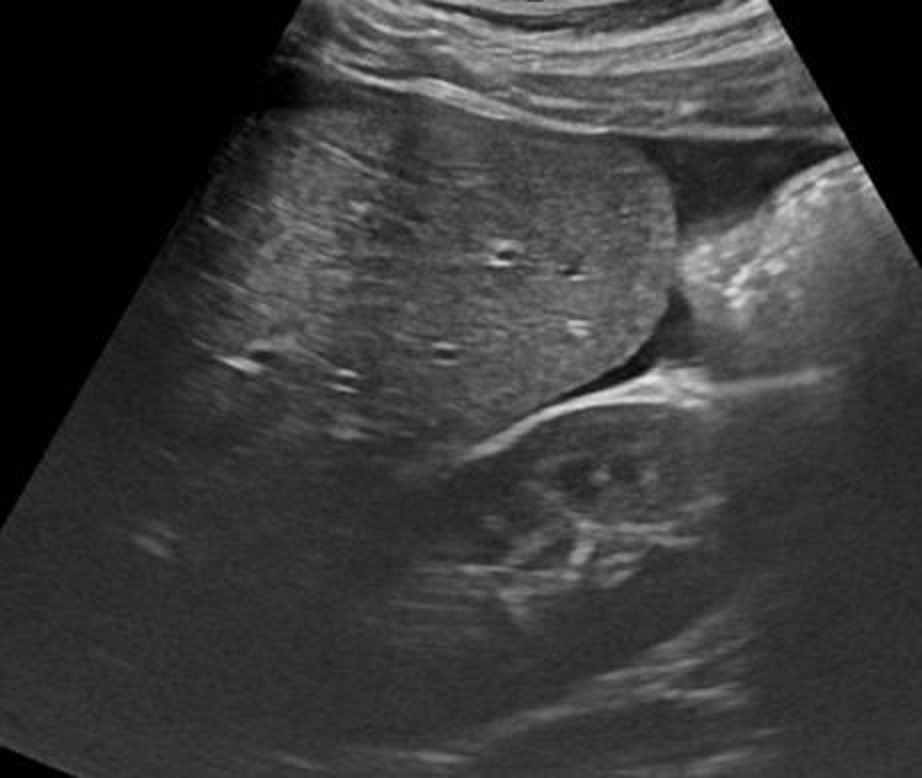

Image

echographique d'une traumatisme de la rate avec

aspect hemoperitoine localiuse peri-hilaire

splenique . |

Image echographique d'une autre

traumatisme de la rate de grade II avec aspect

de laceration casulaire profonde et des hematomes

hypoechogene intra-patenchymateuse .

Complication hemoperitoine peri-capsulaire localise

peut en s,observer ( fleche blanche ) |